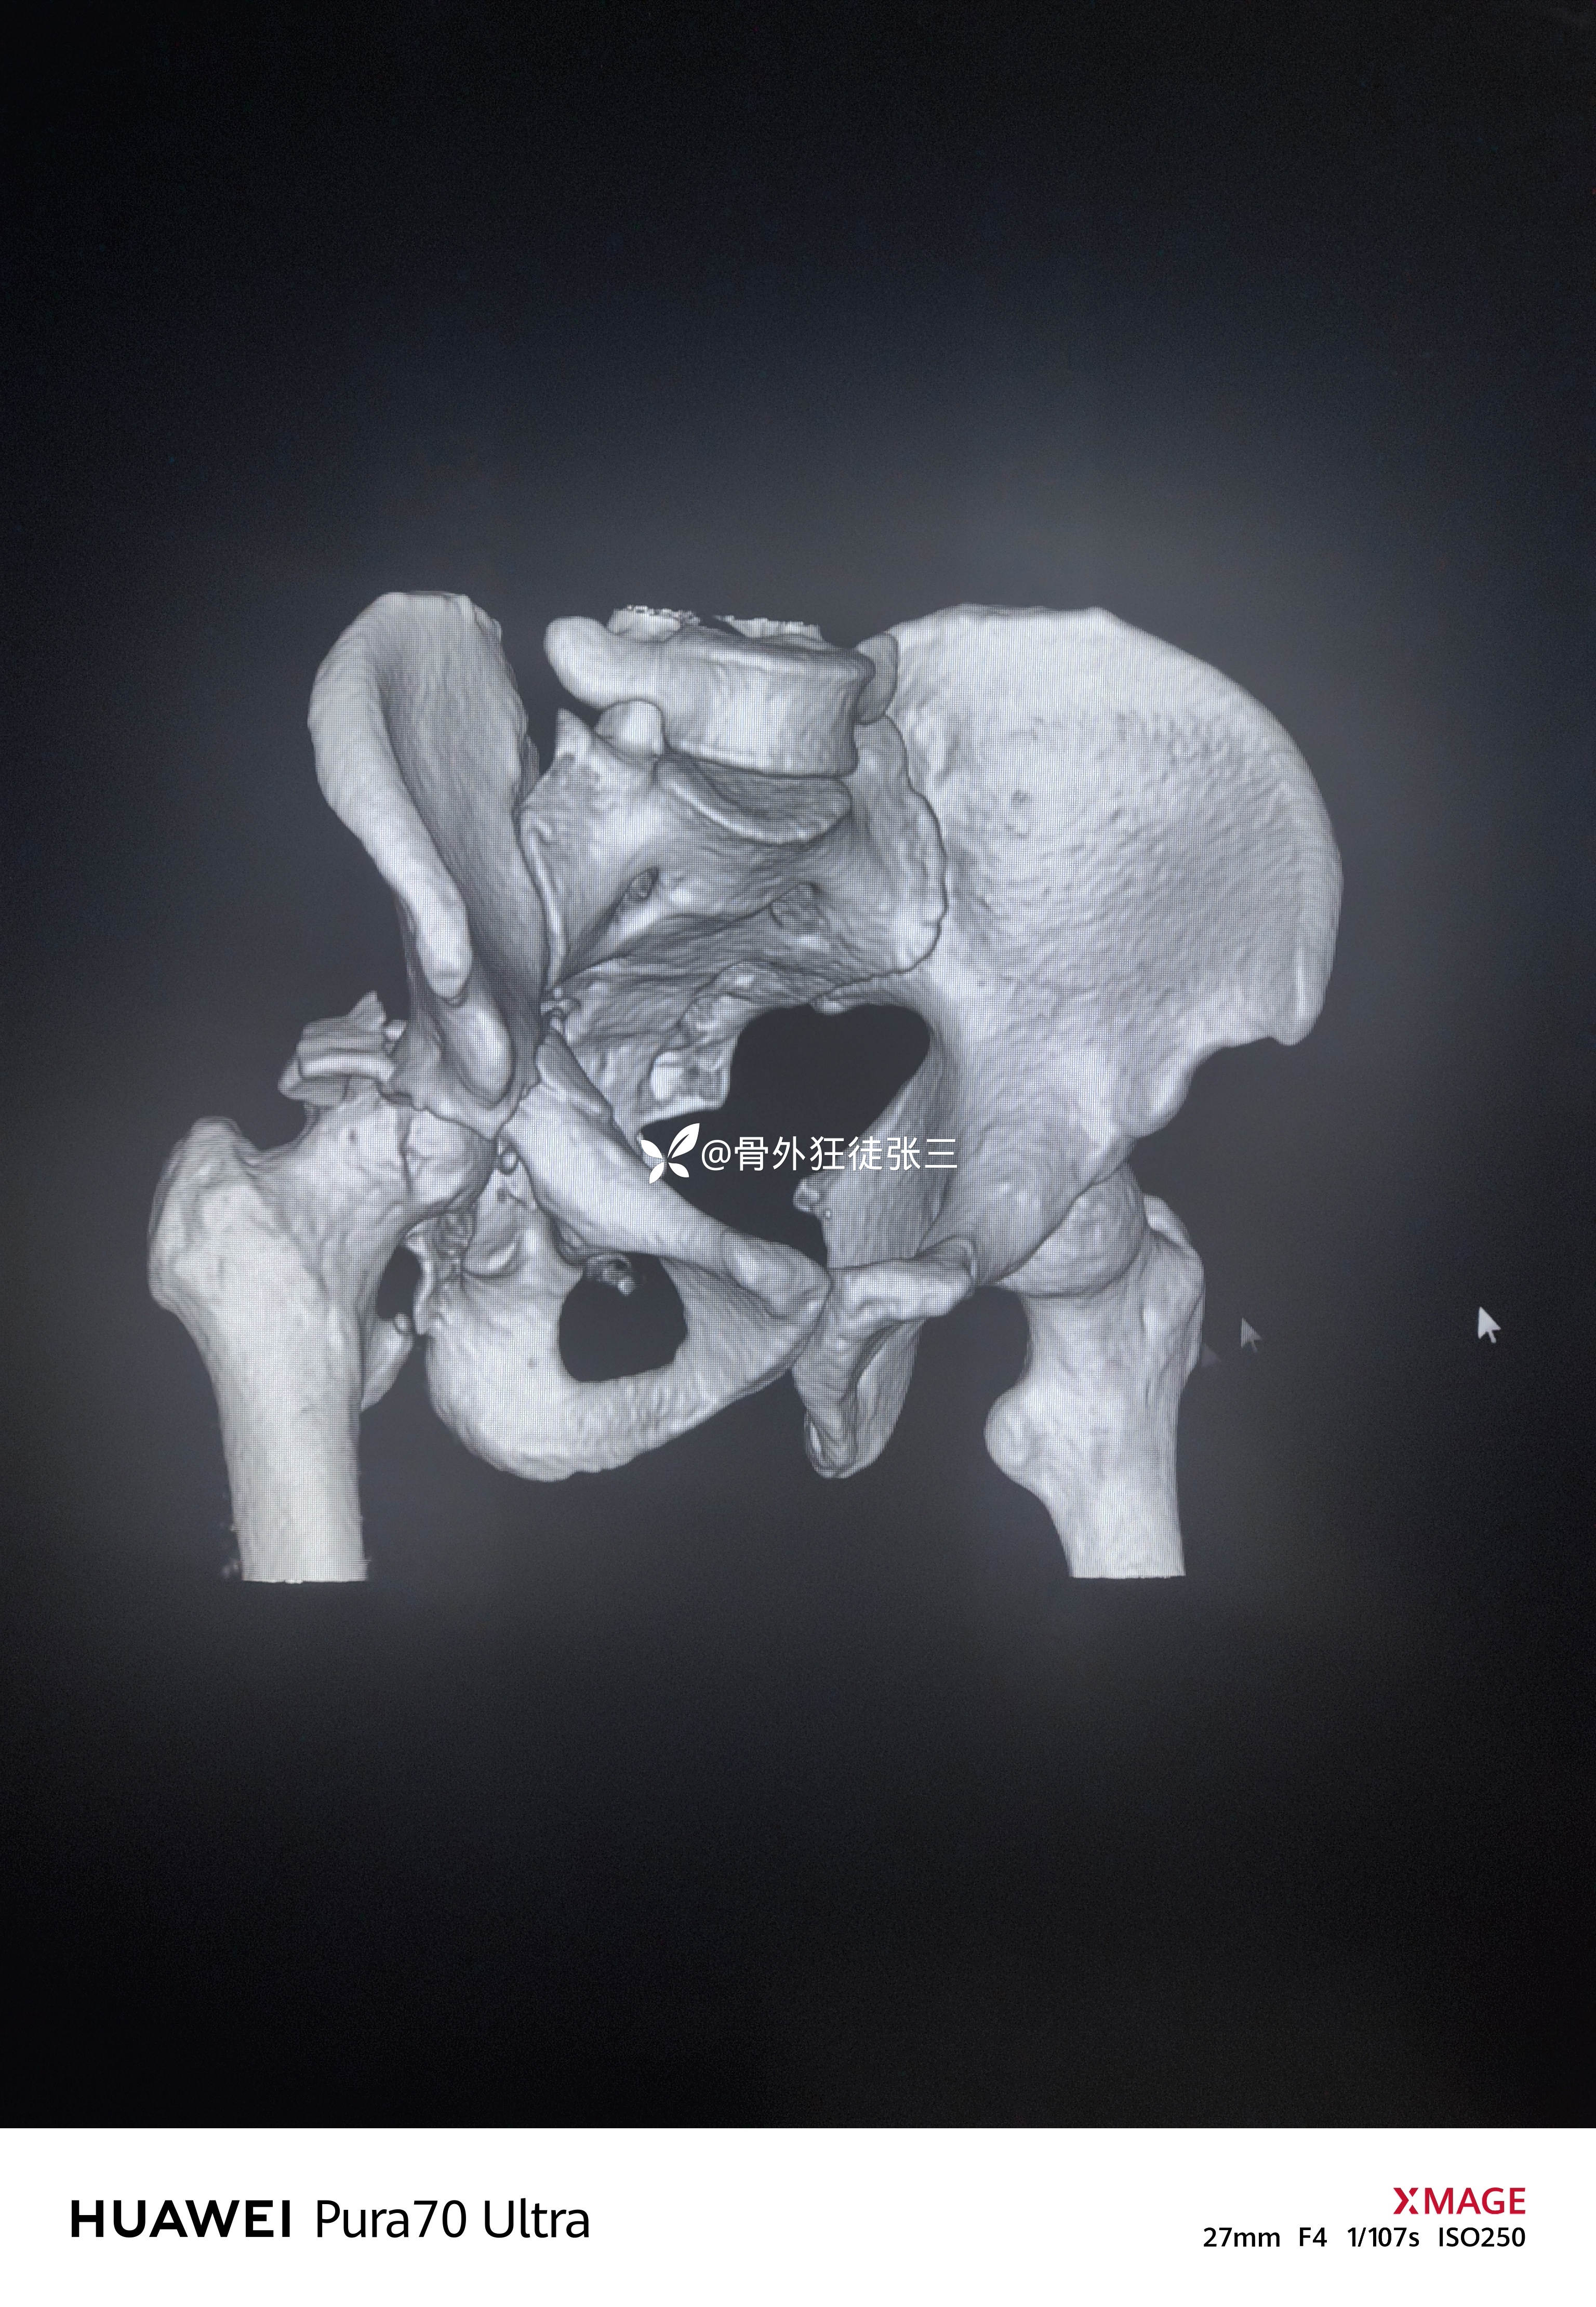

髋关节脱位合并髋臼骨折

髋臼骨折拟二期手术

2,髋臼骨折手术时机?入路?